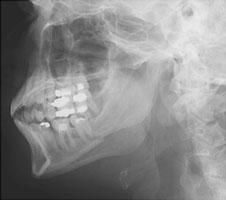

- Click on the image for a larger versionALateral radiograph of the mandible. Multiple fractures are seen.